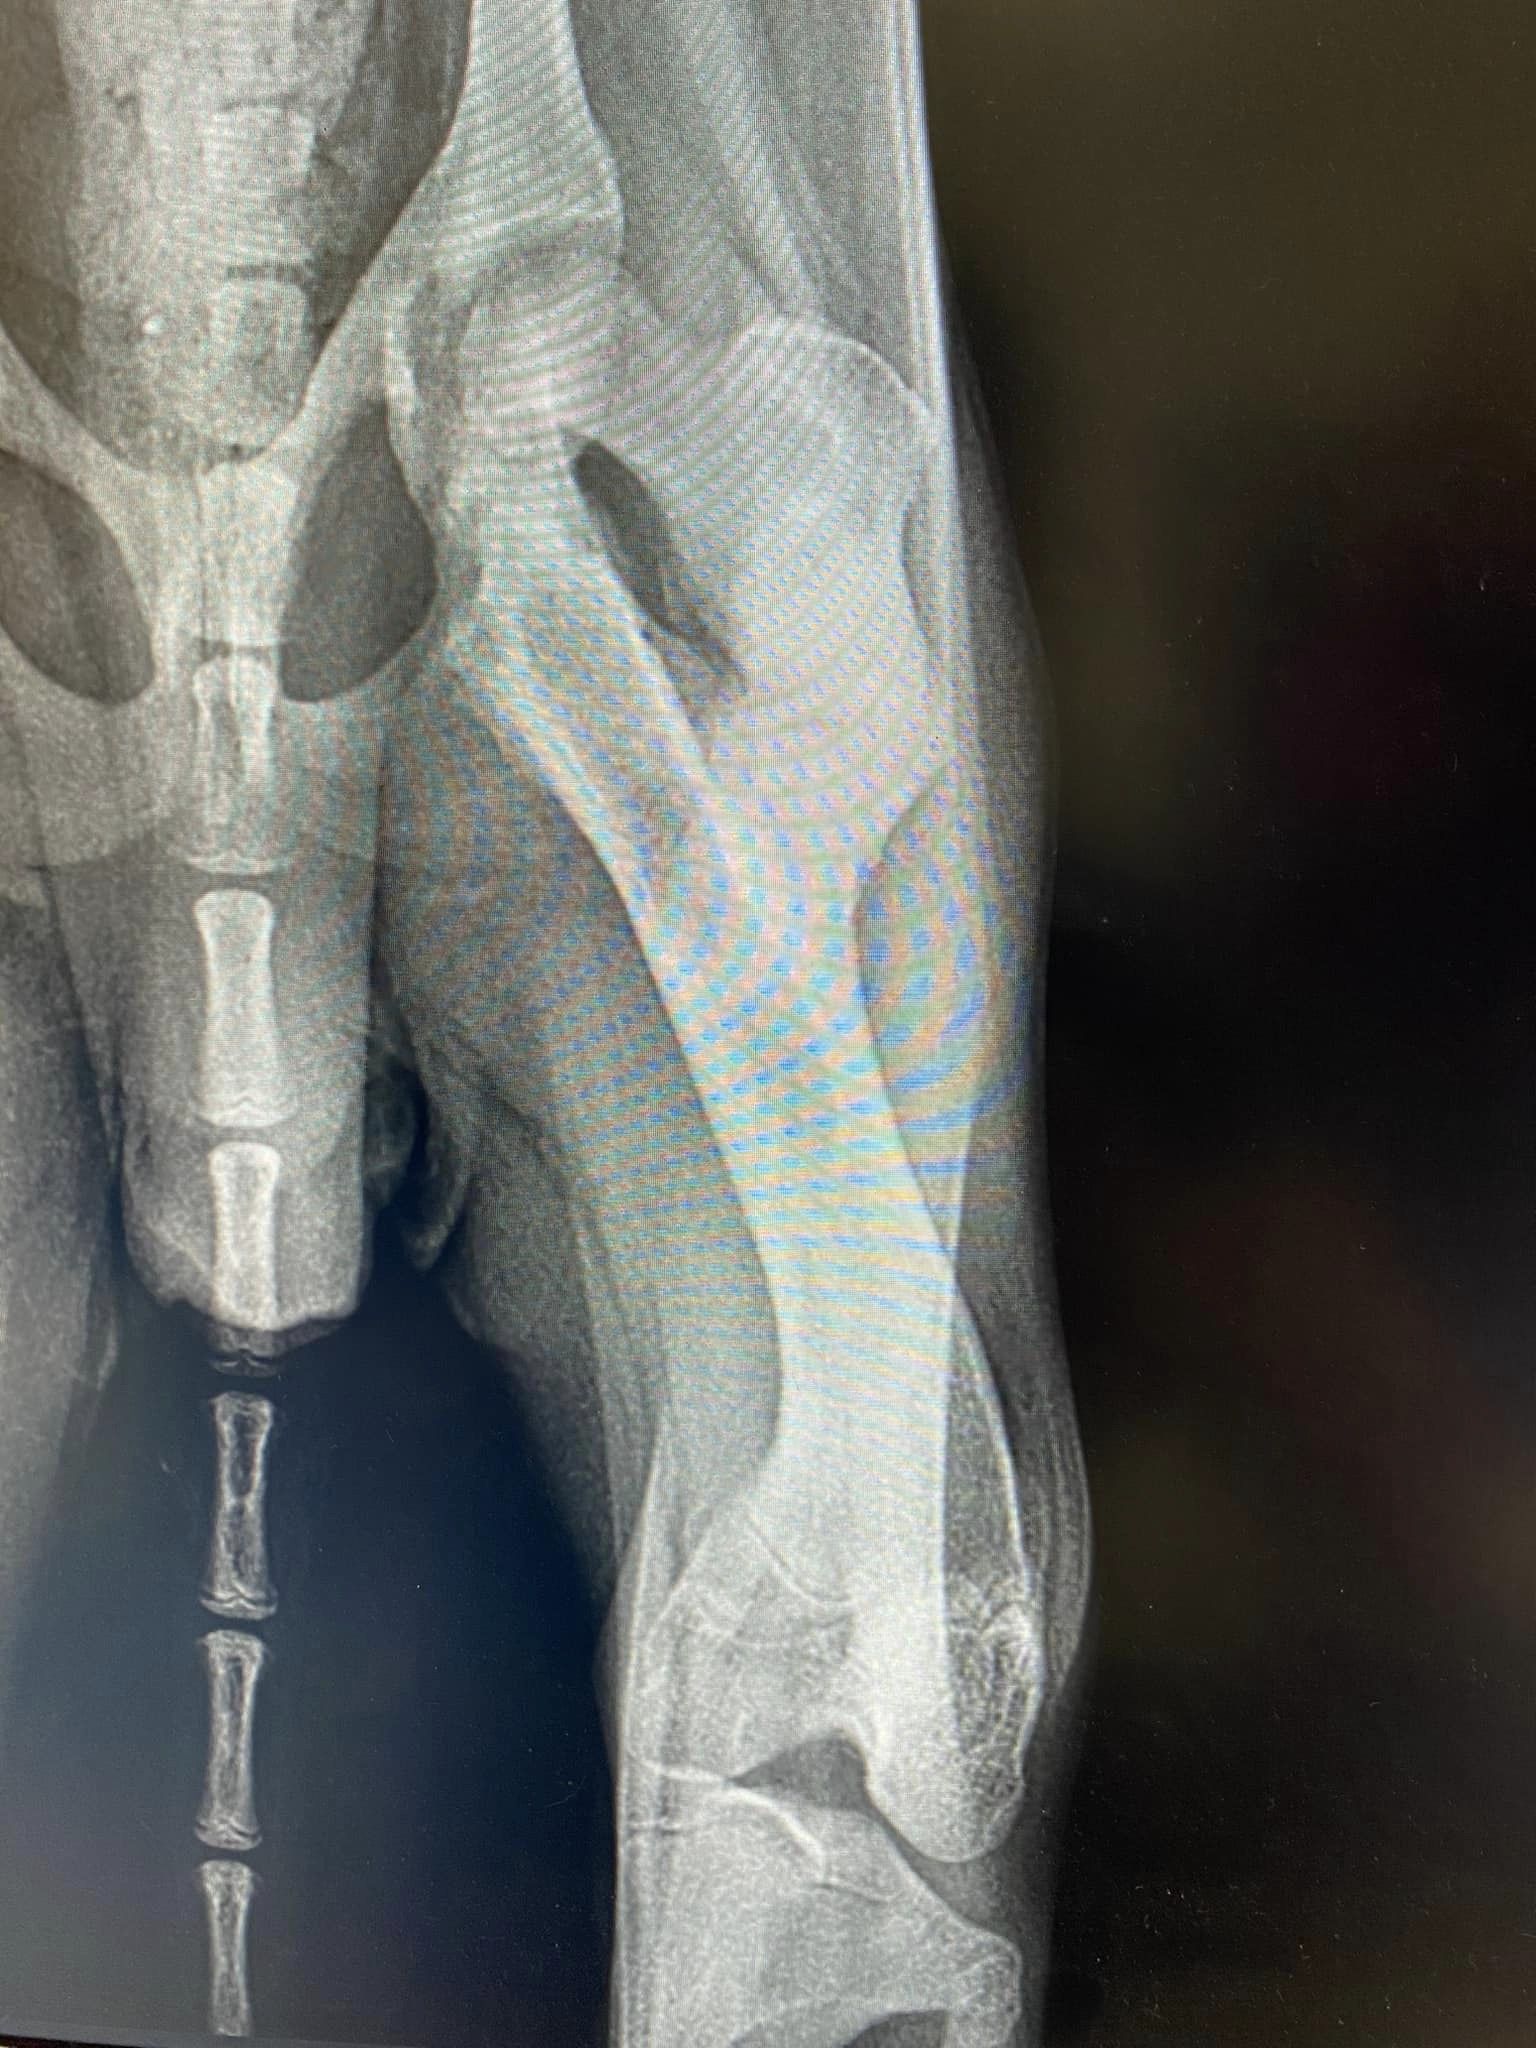

Zastosowanie płyty mostującej 1 lutego 202318 grudnia 2023 Zastosowanie naszej płytki mostującej, cieszy bardzo! Pozdrawiamy specjalistów z Przychodnia weterynaryjna „Kiełbowicz” ! Śledź nas na: